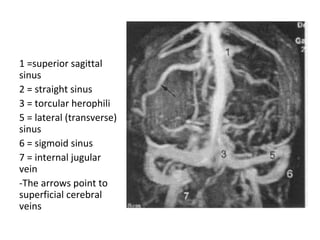

1 =superior sagittal sinus

2 = straight sinus

3 = torcular herophili

4 = vein of Galen

5 = lateral ( transverse )

sinus

6 = sigmoid sinus

7 = internal jugular vein

8 = internal cerebral vein

9 = basal vein of Rosenthal

The arrows point to

superficial cerebral veins